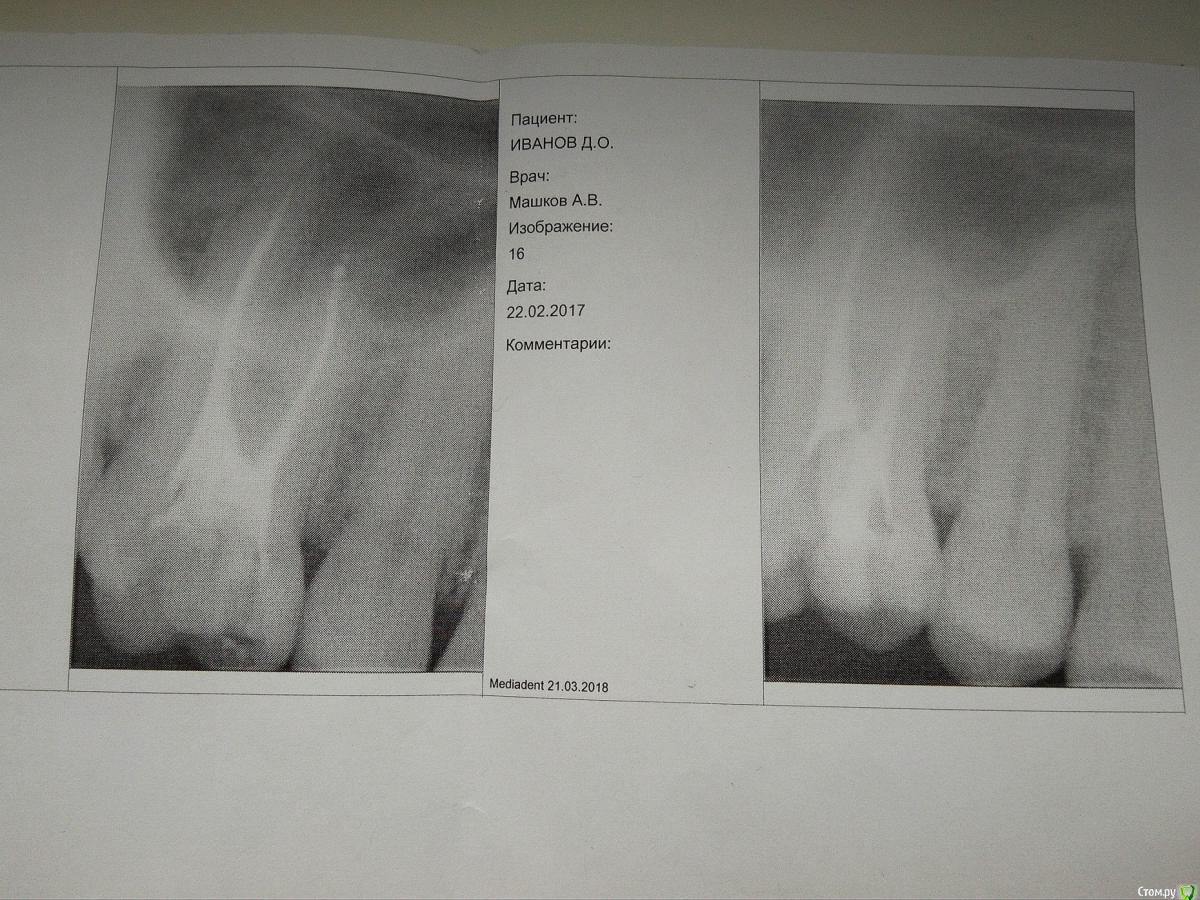

Dima87 Опубликовано 21 марта, 2018 Автор Поделиться Опубликовано 21 марта, 2018 (изменено) Уважаемые, с Вашего позволения подниму тему. Спустя 8 месяцев после пломбировки зуб все таки перестал щелкать. Сейчас, то есть спустя год после лечения, появились неприятные симптомы в области этого зуба при сильном сжимании челюсти и при жевании твердой пищи, а именно: периодически, но не всегда отдает в область носа, ощущается чувство давления в области корня зуба. В покое зуб не беспокоит. Понимая, что это нездоровые симптомы обратился к стоматологу в ведомственную поликлинику. Сделал ОПТГ по причине возникшей сложности сделать прицельный снимок зуба с учетом специфики местного визиографа - на снимок не попадал самый длинный корень зуба. Стоматолог не увидел проблем, сославшись на то, что корень зуба находится в в/ч пазухе и все описанные мною симптомы это норма. С декабря месяца 3 раза переболел ОРЗ (ОРВИ?), хотя на протяжении 20 лет болел 1 раз в год, а то и реже, появился хронический тонзиллит со стеканием слизи в носоглотку, что дало повод обратиться к отоларингологу. Сделав RG пазух носа была выявлена киста в альвеолярной бухте в/ч пазухи. 20.03 сделал МСКТ придаточных пазух носа. В заключении - КТ признаки кисты (одонтогенной?) правой верхнечелюстной пазухи, в области верхушки небного корня 16 зуба с запломбированным каналом выявляется мелкая киста-гранулема размером 9х13х13мм, плотностью до 21едН. Признаков деструкции костных стенок не наблюдается.Прикладываю прицельные снимки после пломбировки каналов зуба годовалой давности и свежий ОТПГ снимок.В моем понимании именно зуб послужил причиной возникновения кисты в пазухе. Требуется ли дентальное КТ для подтверждения одонтогенного происхождения кисты. Посоветуйте, пожалуйста, что делать с этим зубом. Изменено 21 марта, 2018 пользователем Dima87 Ссылка на комментарий